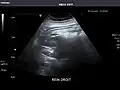

Right kidney -